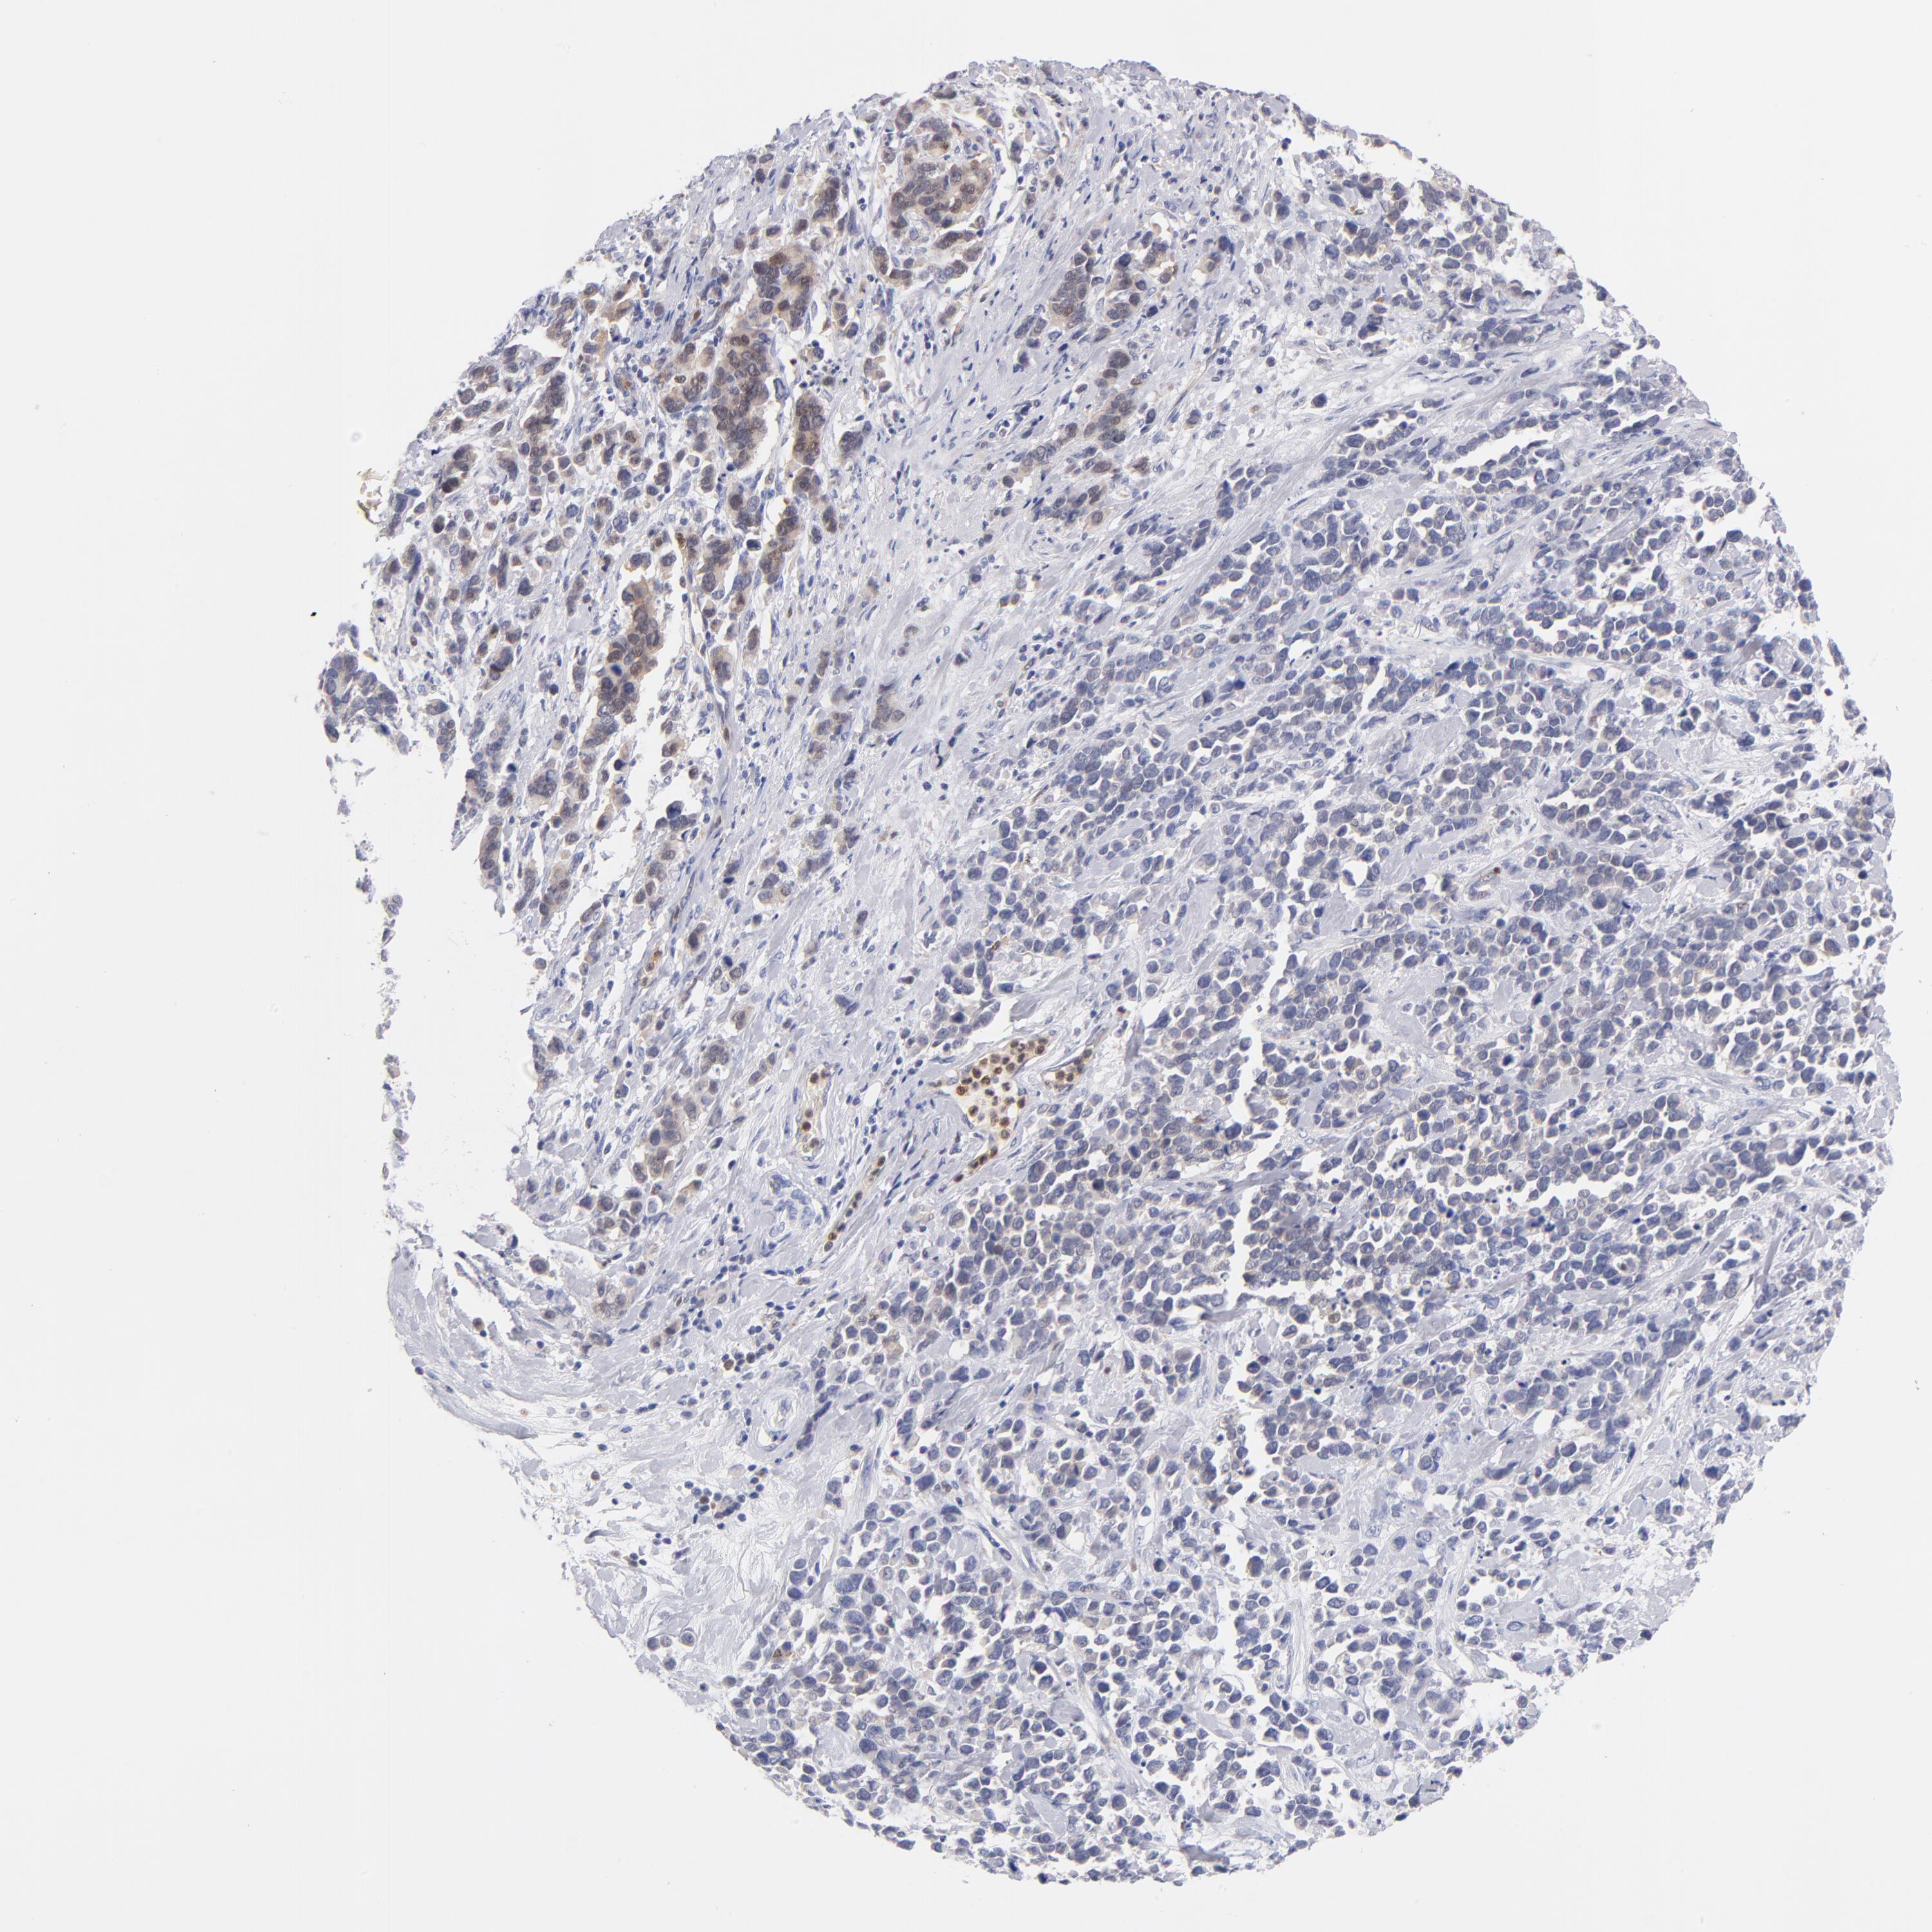

STOMACH CANCER - Protein expressioni

A mouse-over function shows sample information and annotation data. Click on an image to view it in a full screen mode. Samples can be filtered based on level of antibody staining by selecting one or several of the following categories: high, medium, low and not detected. The assay and annotation is described here.

Note that samples used for immunohistochemistry by the Human Protein Atlas do not correspond to samples in the TCGA dataset.

Antibody stainingi

Antibody staining in the annotated cell types in the current human tissue is reported as not detected, low, medium, or high, based on conventional immunohistochemistry profiling in selected tissues. This score is based on the combination of the staining intensity and fraction of stained cells.

Each image is clickable and will lead to virtual microscopy that enables deeper exploration of all samples and also displays staining intensity scores, fraction scores and subcellular localization as well as patient and tissue information for each sample.

Antibody HPA000722

Antibody CAB003771

Staining

High

Medium

Low

Not detected

Intensity

Strong

Moderate

Weak

Negative

Quantity

>75%

75%-25%

<25%

None

Location

Nuclear

Cytoplasmic/membranous

Cytoplasmic/membranous,nuclear

Adenocarcinoma, NOS